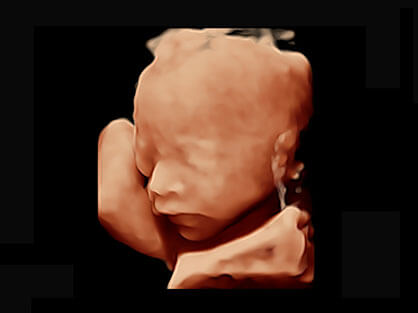

0.5mm厚度的薄层切片显像,可清晰显示微小病灶的连续断面。

可同时显示组织结构表面和内部的轮廓信息,达到透视效果,为临床提供更丰富的诊断信息。

自动获取标准切面,自动完成测量,帮助医生快速完成检查,同时提升测量准确性。

宽频带腹部凸阵探头和腹部容积探头、大角度腔内探头和腔内容积探头、独特的生殖专用曲柄探头,为妇产应用提供全面诊疗方案。

卵泡结构的自动识别和测量,可显示多组测量数据。

大角度腔内容积探头,可完整包络子宫及盆底结构,充分展示组织结构毗邻关系。